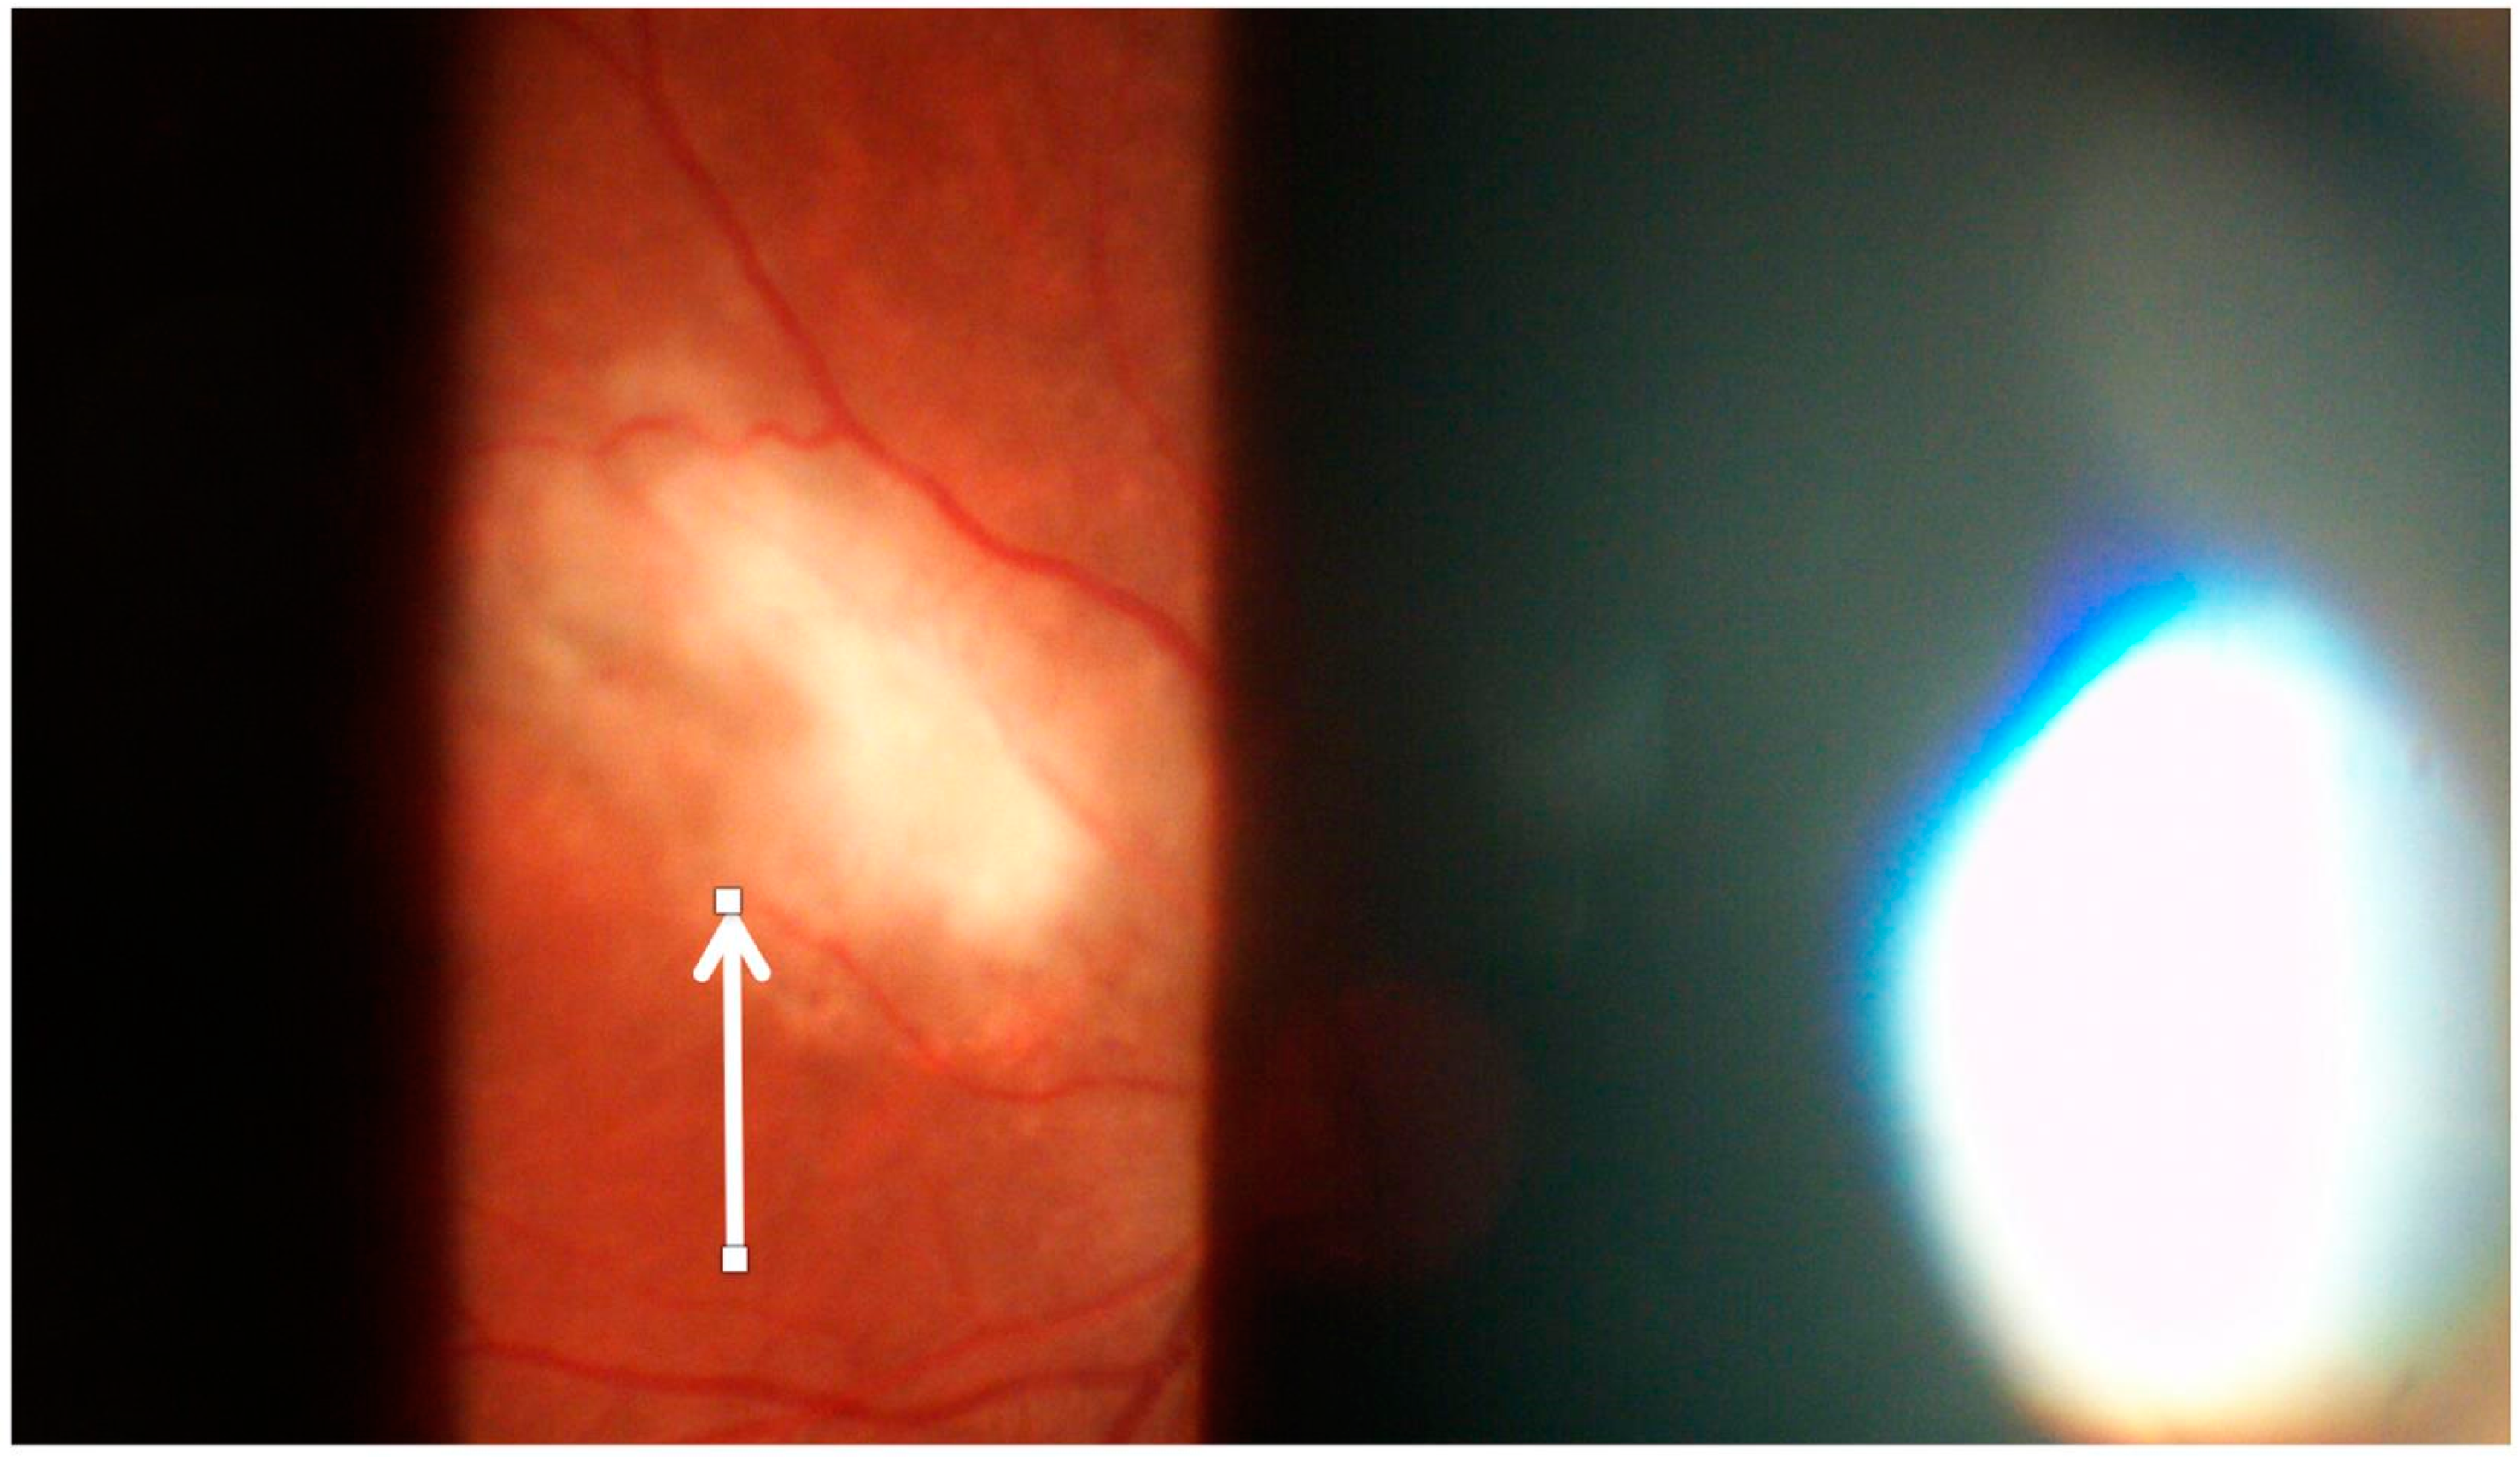

- Egan, R.A.; Hills, W.L.; Susac, J.O. Gass plaques and fluorescein leakage in Susac Syndrome. J. Neurol. Sci. 2010, 299, 97–100. [Google Scholar] [CrossRef]

- Bagaglia, S.A.; Passani, F.; Oliverio, G.W.; Inferrera, L.; Menna, F.; Meduri, A.; Mazzotta, C. Multimodal Imaging in Susac Syndrome: A Case Report and Literature Review. Int. J. Environ. Res. Public Health 2021, 18, 3435. [Google Scholar] [CrossRef]